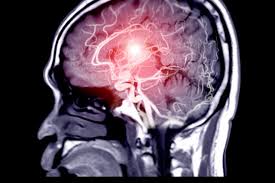

Cerebrovascular surgery involves medical procedures that treat conditions affecting blood vessels in the brain. These conditions include aneurysms, arteriovenous malformations, and blocked arteries. Consequently, surgery aims to restore proper blood flow and prevent strokes or neurological damage.

Cerebrovascular surgery addresses several vascular disorders. Aneurysms can rupture, causing life-threatening bleeding, while arteriovenous malformations may lead to seizures or hemorrhage. Meanwhile, narrowed arteries may restrict blood flow, increasing stroke risk.

Diagnosis begins with a detailed neurological assessment and evaluation of symptoms. Doctors examine reflexes, coordination, motor skills, and cognitive responses. Meanwhile, imaging techniques such as CT angiography, MRI, or digital subtraction angiography help visualize brain vessels. Furthermore, blood tests may evaluate risk factors like cholesterol levels and clotting tendencies. Therefore, comprehensive diagnostic evaluation ensures accurate identification of the affected vessels and surgical planning.